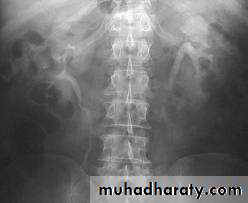

Schistosomiasis

Infestation by s.hematobiumCalcification is most important feature, mainly in bladder & lower ureters , but may involve whole ureters .

In early stage inflammation may cause cobble stone appearance.

Bladder capacity not affected.Ddgx of bladder calcification :